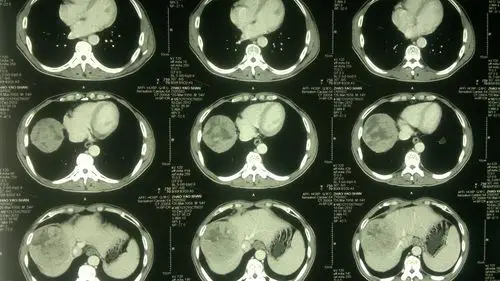

原发性肝癌的影像表现

原发性肝癌的影像诊断影像天地